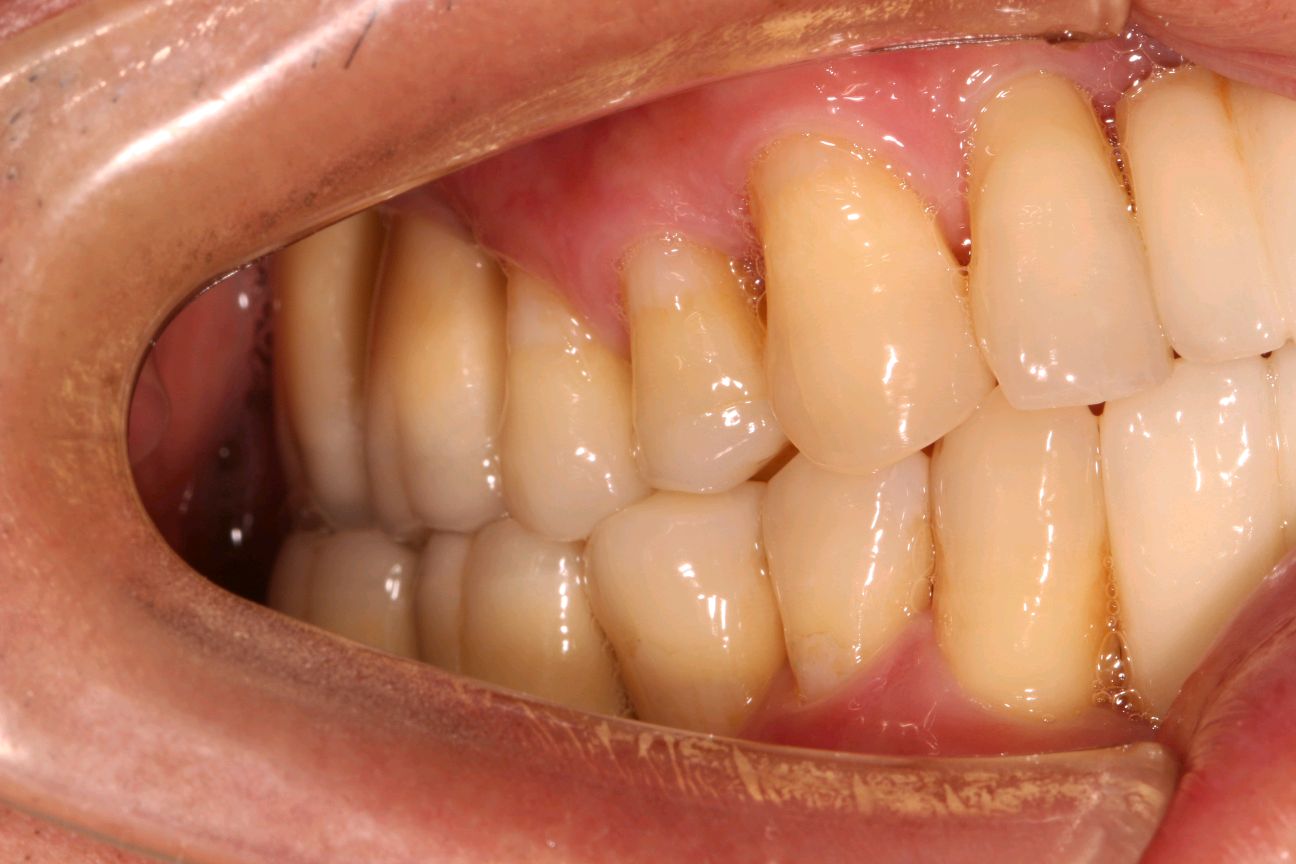

术中全景片